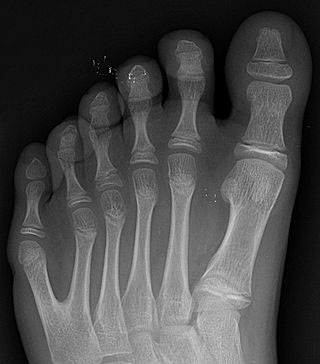

Polydaktylian yleisyyttä tutkittiin analysoimalla 96 luurankoa Pueblo Boniton 800–1100 -luvuille ajoittuvalta kohteelta. Vainajien joukosta löydettiin kolme yksilöä, joilla on kuudes varvas oikeassa jalassa. Prosentuaalisesti määrä on paljon, sillä se edustaa noin 3,1 % kohteen asukkaista. Nykyamerikkalaisilla polydaktylian esiintymisyleisyys vaihtelee 0,2–1,4 %:n välillä.

Pueblo Boniton asumuksia on usein koristeltu käsi- ja jalkapainantein, joiden joukossa on toisinaan havaittavissa ylimääräisiä varpaita. Kuusivarpaisten painanteiden havaittiin olevan hieman yleisempiä kivaksi kutsuttujen rituaalihuoneiden sisäänkäyntien yhteydessä, ja kuusivarpaiset henkilöt oli myös yleensä haudattu näiden huoneiden lähistölle. Yhden vainajan kuusivarpaisessa jalassa oli myös koristeellinen nilkkakoru, jolla voi olla erityistä symboliikkaa.